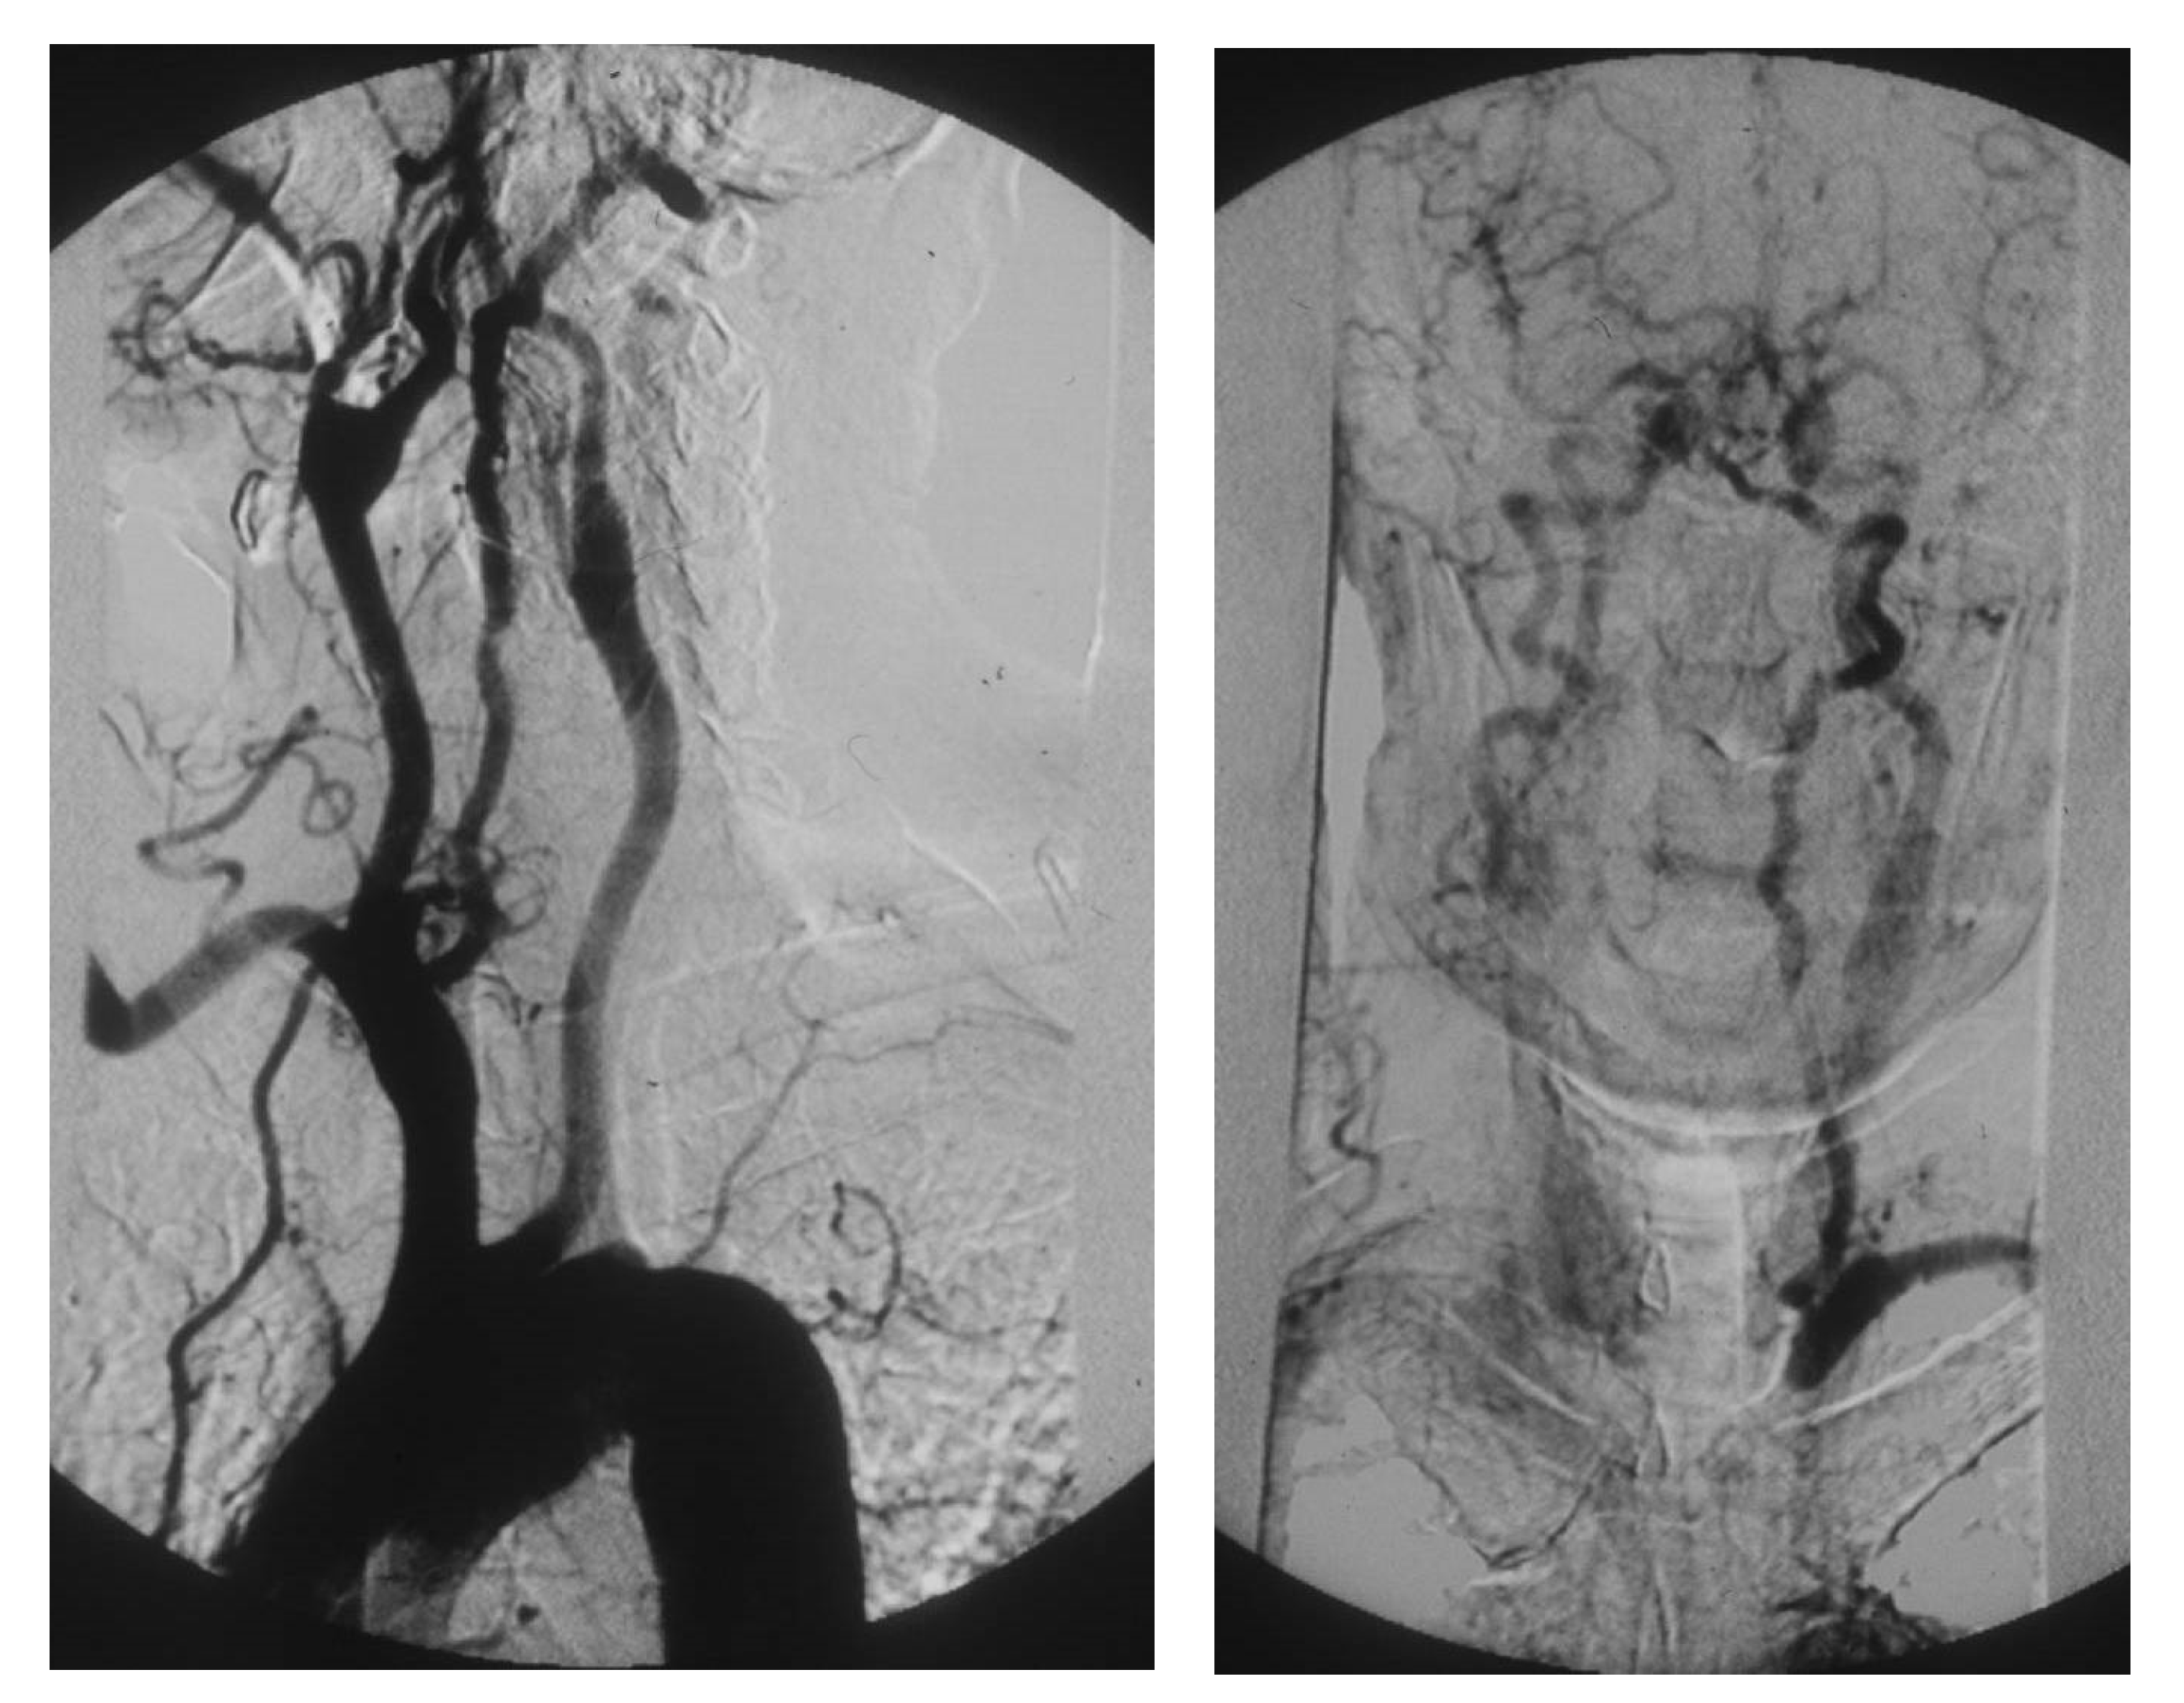

PAAs should be detected, not much for the risk of rupture, which is rare, but for their risk of embolization and thrombosis. The physiologic flexion of the knee can act as a tremendous stress for the parietal thrombus of the PAA, potentially causing paroxysmal, multiple, and insidious episodes of asymptomatic microembolization to the tibial arteries (Figure 8).

Figure 8. Arteriography showing popliteal artery aneurysm. The physiologic flexion movement of the knee can dislocate part of the mural thrombus, which embolizes and occludes some tibial arteries, giving rise to clinical pictures ranging from an asymptomatic state to intermittent claudication, or chronic limb-threatening ischemia, or acute limb ischemia.